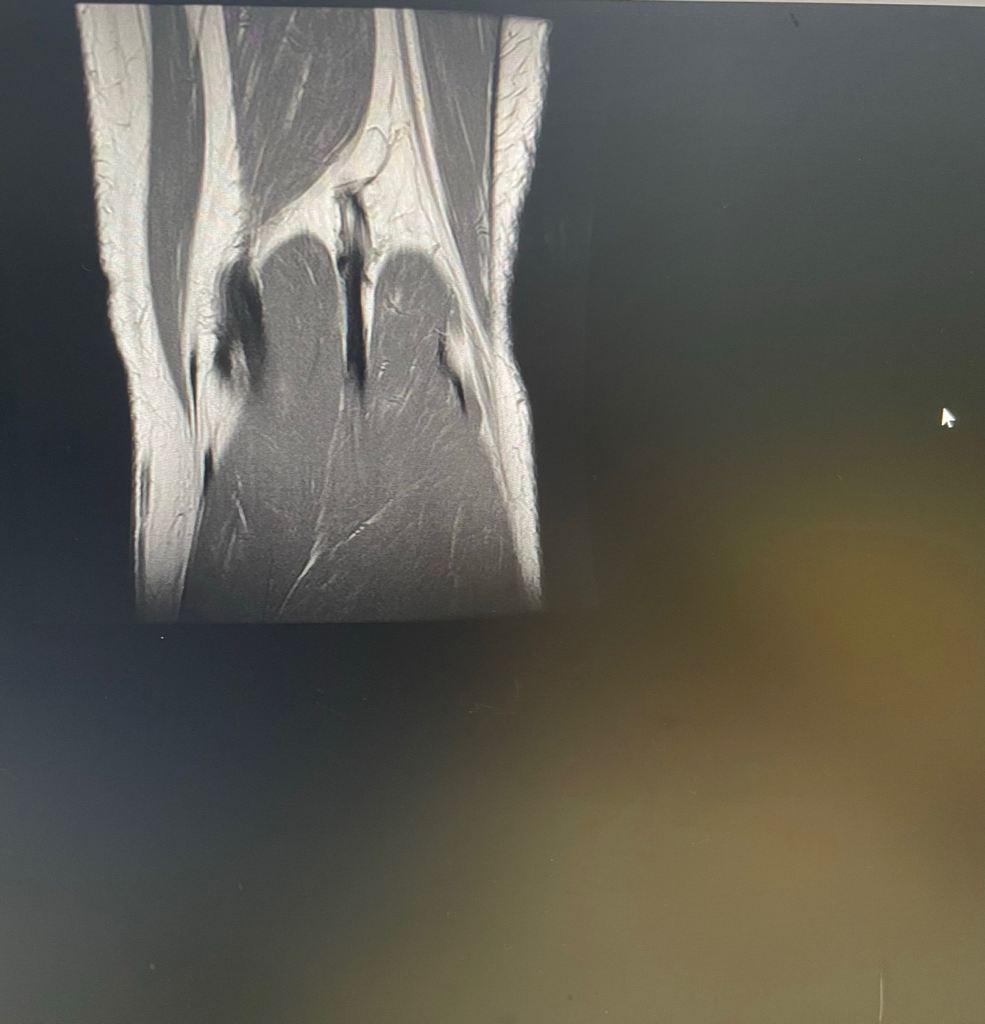

무릎 mri 원형원골인지 봐주실 수 있을까요

무릎이 너무 자주 아파서 mri를 찍어봤는데 무릎 연골에 이상이 있을까요

무릎이 선천적으로 원형연골인지 봐주시면 감사하겠습니다

• 1번 째 사진

MRI 판독에는 퇴행성 연골 손상, 바깥쪽 원판형 반월상 연골 이 의심된다고 적혀 있습니다.